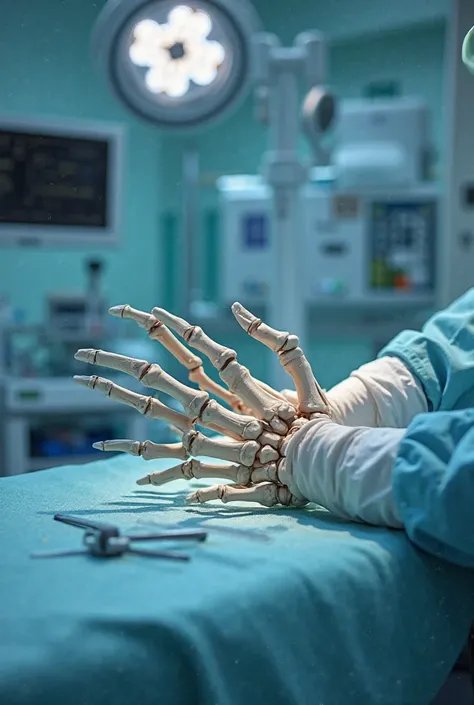

A close-up of an x-ray of a left hand

The skeleton of the hand is a mechanical android